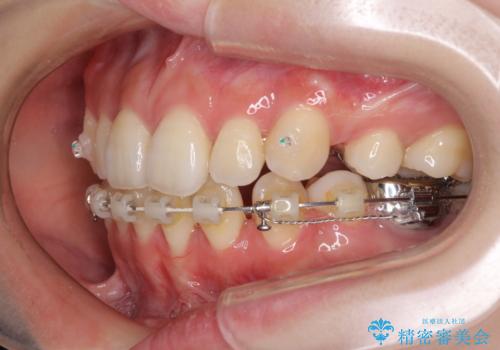

- ハーフリンガル

- 口元の突出感を気にして来院された患者様です。

上下左右の第一小臼歯4本を抜歯して口元を下げる治療計画としました。

裏側矯正特有の抜歯スペースに前後の歯が倒れ込む状態が長く続き、改善に長期間を要しました。